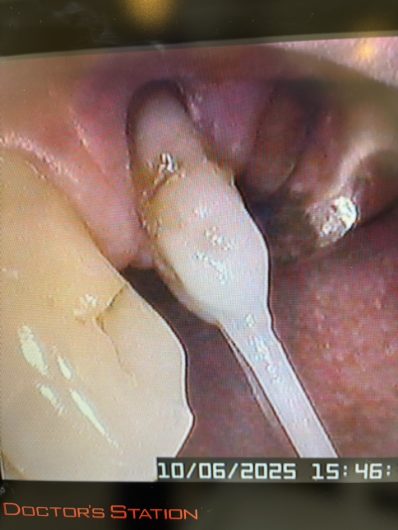

ファイバーポストによる歯根の土台補強

根管治療後、補強のための土台作り。

ファイバーポストは歯の柔らかさに近いしなりを持ち尚且つ接着剤が歯に染み込んで固まるので歯との一体感が抜群です。そのため長期に渡り歯根を守る役割を果たしてくれる強い味方なんです。